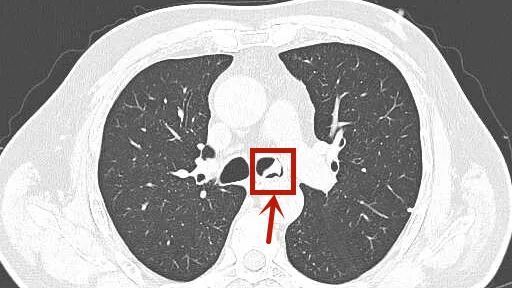

这些不对劲,让子女们都担心不已,赶紧把周大伯送到了杭州市第三人民医院呼吸内科。接诊的丁凌医生询问后,怀疑周大伯的气管内存在异物,第一时间安排他做胸部CT检查。而结果显示气管内有高密度影,高度异物可能!

呼吸科主任冷报浪仔细阅片,立即联系内镜中心,紧急为周大伯安排纤维支气管镜检查:气管镜经声门进入,果然发现一异物横跨在气管分叉与左主支气管交界处。

再仔细一瞧,它质硬,带小钩,大小约3*2*1cm,这不正是周大伯消失的部分假牙么?